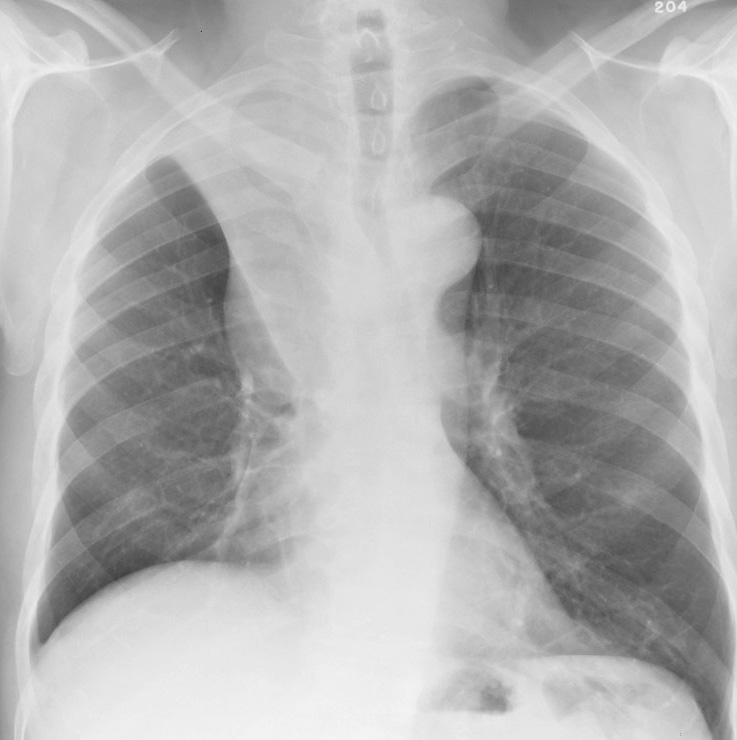

RUL Collapse Case 1 PA